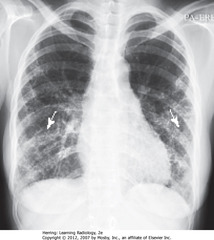

Pneumoconiosis

Inhalation and retention of dust (Assocated with pulmonary fibrosis (radiograph) and tumors